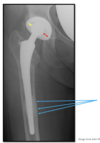

How well did you know this?

When doing a portable hip arthroplasty what must you NEVER do how much of the arthroplasty must we include?

- Cross pt. legs (often have a pillow between the legs) Flex hips past 90 degrees *need at least 1" past metal prosthesis (may have # under it)

Not straight down (# below arthroplasty) Distance between head of femur and acetabulum (need equal distance)